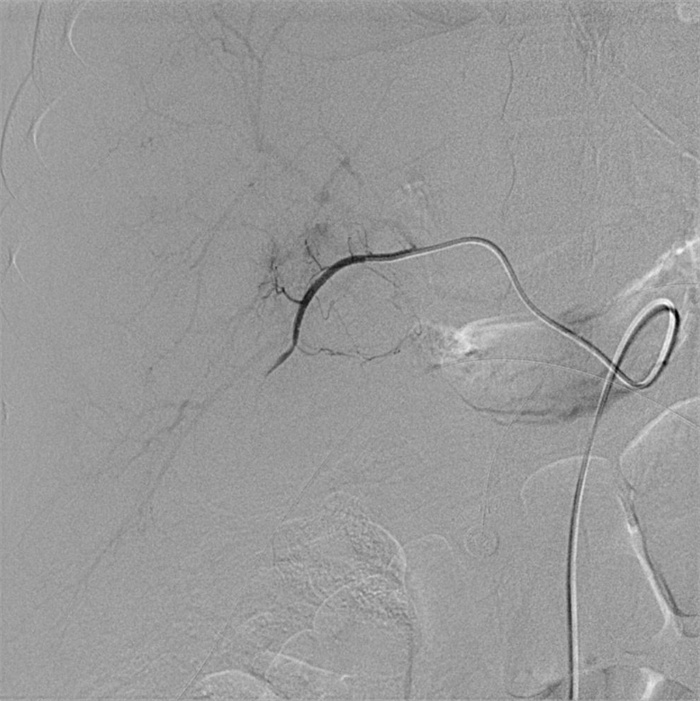

入院第57天,患者再次出现暗红色血便,伴阵发性右上腹痛,无发热、呕血,症状与之前相同。鉴于患者有活动性出血,再次复查胃镜:慢性浅表性胃炎伴糜烂。复查肝功能:γ-GT 844 U/L,TBil 43.6 μmol/L,NCBil 16.6 μmol/L,CBil 27 μmol/L,肝功指标再次回升,γ-GT、CBil明显升高,提示可能出现胆道梗阻。肝胆脾胰腺彩超复查:胆囊肿大、胆囊陈旧性稠厚淤胆(较前无明显变化),胰腺稍大并不均质改变。复查上腹CT:AP复查情况与之前相同,可能有胆囊出血(见图 2)。联合介入放射科行血管造影检查,常规局部麻醉下采用Seldinger技术由右侧股动脉入路,造影发现胆囊动脉分支出血(图 3),超选择胆囊动脉分支用明胶海绵颗粒行栓塞止血(图 4)。同时,行经皮经肝胆囊穿刺置管引流(图 5),病情稳定后带管出院,3月后予以拔除,择期行胆囊切除。

| 胆囊动脉增粗,其分支局部造影剂外溢,未见明显动脉瘤征象 图 3 胆囊动脉造影 |

胆囊动脉出血是罕见的胰腺炎血管并发症,确切的病理基础尚不清楚,推测其出血的机制主要继发于胰管释放的胰酶侵蚀及炎症刺激损伤血管壁[4]。介入放射科的共同参与在复杂胰腺炎的救治中有着重要作用[8],胆囊动脉出血难以被常规的检查发现,尤其是经常规治疗后患者仍有活动性出血时,选择性血管造影应作为首选方法。血管造影仍然是目前判断有无活动性出血的“金标准”,敏感度可达80%~90%以上[9]。血管造影同时发现异常血管、急性出血病因及部位[10],发现病灶的同时可给予介入治疗,有助于迅速维持血流动力学稳定。